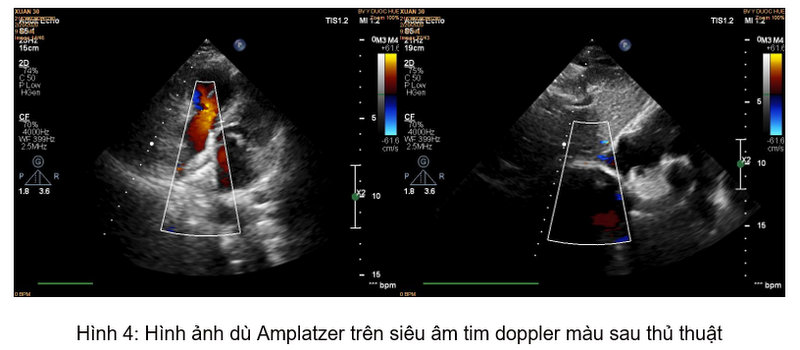

Thủ thuật được tiến hành một cách nhanh chóng, an toàn và không xuất hiện biến chứng. Sau thủ thuật, triệu chứng bệnh nhân cải thiện một cách rõ rệt, không còn hồi hộp, khó thở. Kiểm tra lại trên siêu âm tim doppler màu cho thấy lỗ thông liên nhĩ đã được đóng hoàn toàn, không còn dòng chảy bất thường.